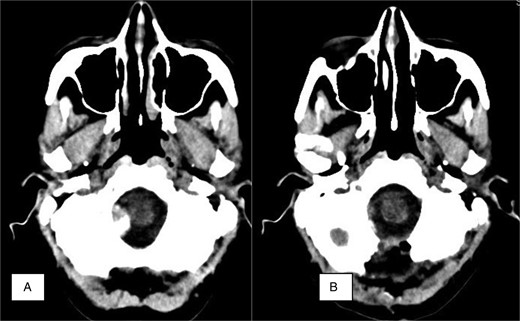

Neuroradiology finding. (A) Axial CT. Preoperative calcified mass at the right foramen magnum resulting in slight displacement of the medulla. (B) Axial postoperative CT showing no residual tumor and bone resection.